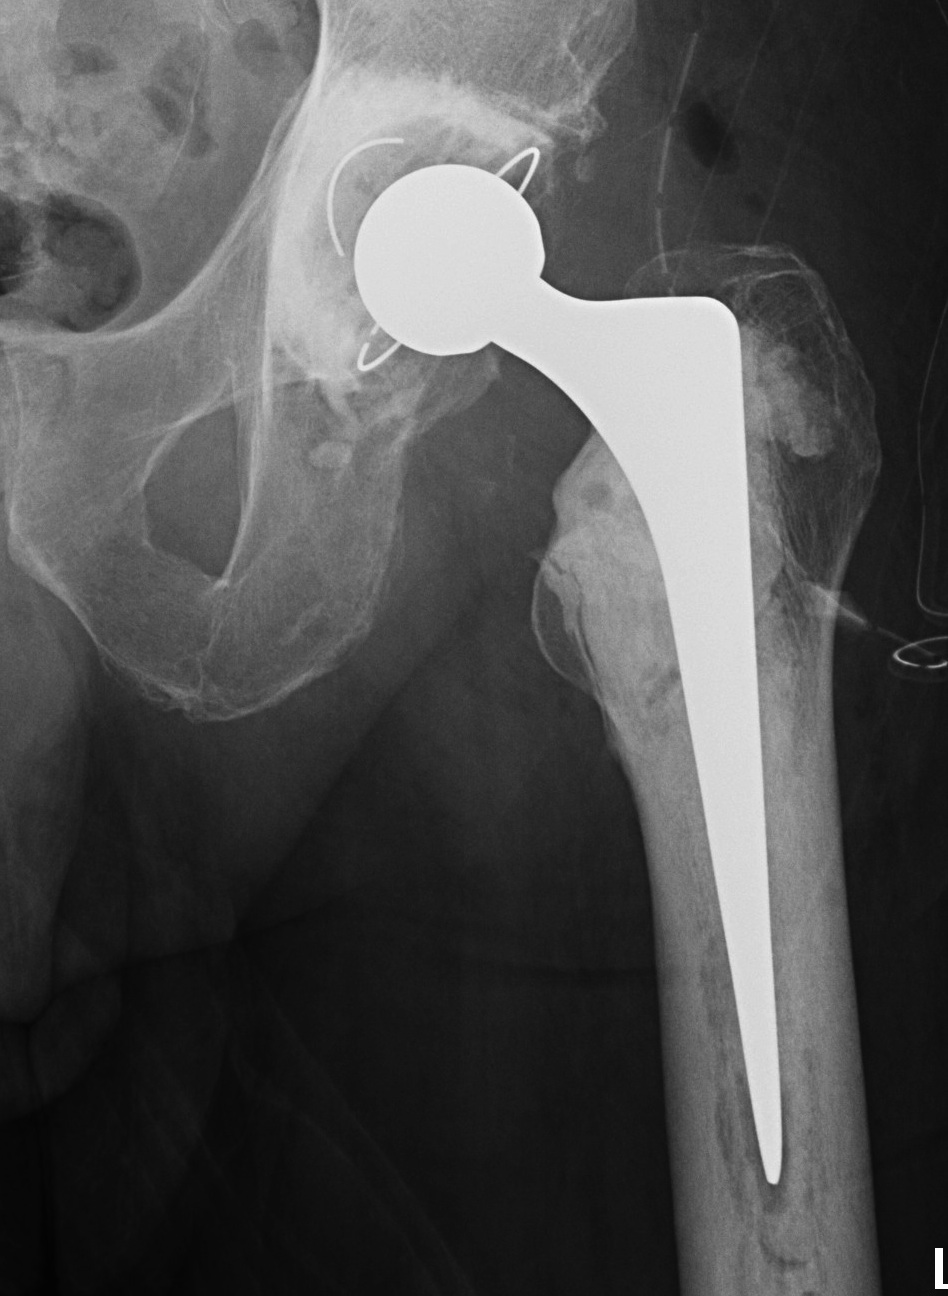

1. Long stem cemented revision femoral stem

2. Extensively porous coated diaphyseal fitting uncemented stem